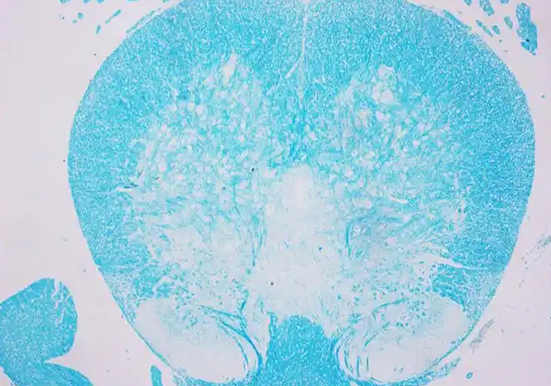

LFB 染色即劳克坚牢蓝(Luxol Fast Blue)染色,是一种常用于显示神经组织中髓鞘结构的染色方法,以下是关于它的详细介绍:

染色原理:LFB 属于铜 - 酞箐染料,是一种酒精溶性染料。髓鞘由髓鞘细胞和细胞膜组成,其成分主要是类脂质和蛋白质,其中的脂蛋白与 LFB 染料发生酸 - 碱反应,脂蛋白碱基取代 LFB 染料的碱基,形成深蓝色沉淀,从而使髓鞘着色。

分化:室温自然冷却后取出切片,自来水洗至呈无色。随后将切片迅速浸入 0.05% 碳酸锂分化液中快速分化 5 秒,然后取出切片立即置于 70% 乙醇中快速分化 10 秒,可交替进入 0.05% 碳酸锂分化液和 70% 乙醇中进行分化,及时镜检直至髓鞘呈蓝色、背景无色,最后水洗终止分化。